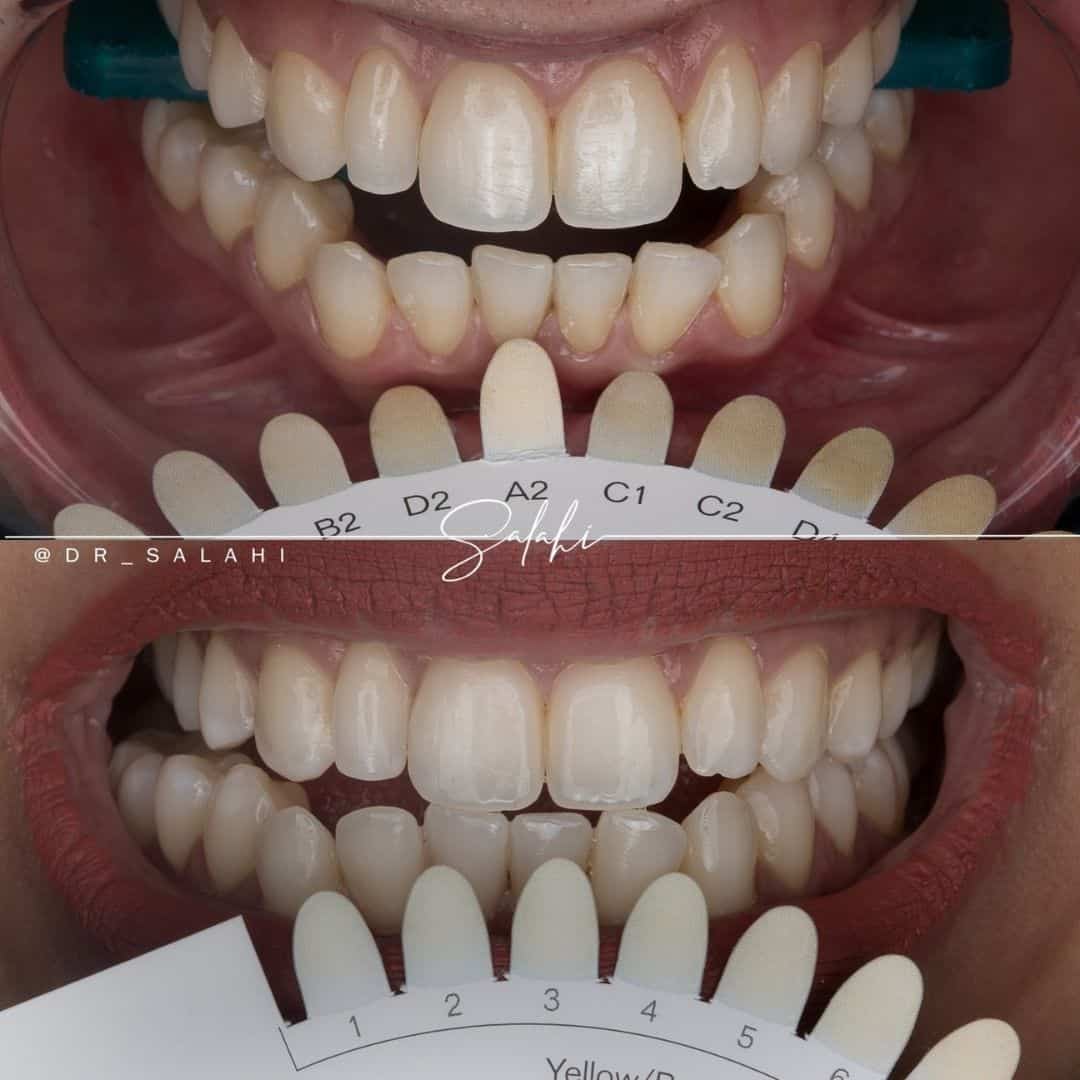

نتائج رائعة لمراجعينا